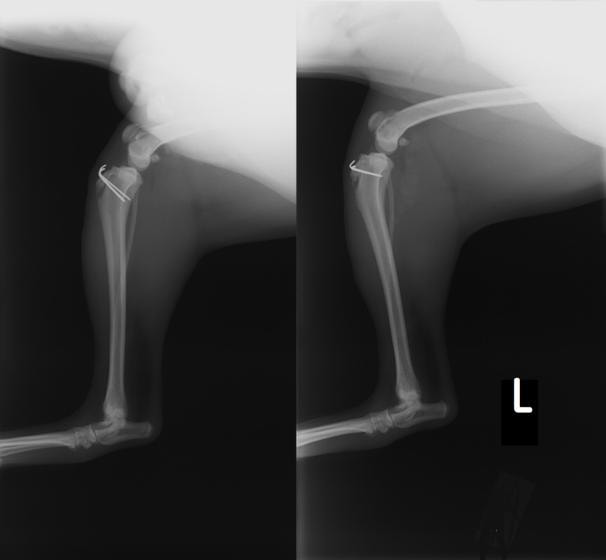

■ 症例20 ポメラニアン 8ヶ月 1.8kg

左右膝蓋骨脱臼 グレードⅢ

2ヶ月前から間欠的跛行が認められ、両膝の膝蓋骨脱臼整復術を行った。

手技は縫工筋及び内側広筋の解放、脛骨粗面の外側転位、滑車ブロック形造溝術、内外側関節包の縫縮を選択し実施した。

右側の膝蓋骨脱臼は上記手技で整復されたものの、左側はそれのみでは膝蓋骨が浮く様子が認められた。その為、PDS縫合糸にて膝蓋靱帯を1糸のみ縫合し、靱帯の縫縮を行った。

膝蓋骨脱臼は膝関節における膝蓋骨の内外側の脱臼と定義されるが、時として単純な内外の脱臼ではなく、膝蓋骨が大きく前方に浮き上がるように脱臼する場合がある。特にトイプードルやポメラニアンといった犬種に多く認められる。

内側脱臼に加えて前方への浮き上がりを矯正する為に、従来より脛骨粗面転移により膝蓋靭帯を外方と下方に引っ張り、固定する方法を選択する。膝蓋骨の前方への浮き上がりが軽度の場合は、従来法ではなく関節包の縫縮で対応していた。しかし、一部の症例で膝蓋骨の動きが悪くなり伸展機構が円滑に機能せずロボット様歩行になるケースがあった。

その為、膝蓋靭帯自体を縫縮する方法を採用した。この方法により、膝関節の伸展機構を妨げず膝蓋骨の軽度の浮きを矯正することが可能となった。

本症例の経過は良好である